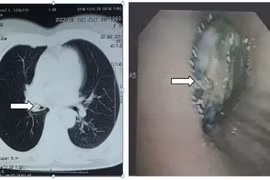

Ăn quất hồng bì, người phụ nữ bị sặc dị vật vào phổi

Người dân cần đặc biệt lưu ý khi ăn các loại quả có hạt trơn, tròn như vải, nhãn, quất hồng bì… bởi nguy cơ sặc dị vật vào đường thở rất cao.